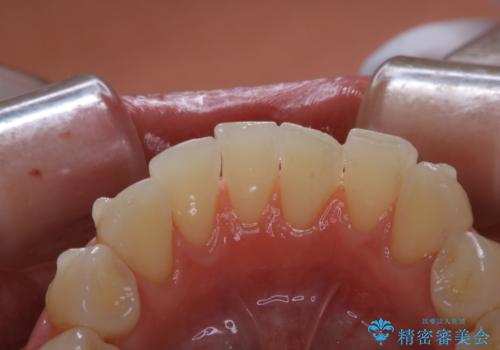

- インビザライン矯正治療中にステインが気になるとのことで来院されました。全体的にステインが付着していたため自費クリーニングPMTC(60分コース)を行いました。

インビザライン矯正治療中は、ご自身の歯にアタッチメントという突起物(効率的に歯の移動を行うため)をつけます。そのため、通常時よりもステインが付きやすい状態になることがあります。

インビザラインは透明なマウスピースなので、ご自身の歯にステインなどが付着していると、見た目に影響してしまうことがあります。

矯正治療中の虫歯・歯周病・口臭予防としても、定期的にPMTCを行うことが大切です。